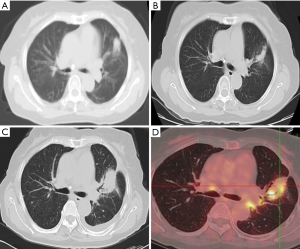

The accumulated sensitivity and specificity of HRFs are shown in Table 7. Patients with only 1 HRF showed high sensitivity (100%) and low specificity (52.80%), and the specificity increased with the number of HRFS while the sensitivity decreased. The CT images with diagnosis, follow-up, and relapse of 1 patient are shown in Figure 2. The tumor relapse was confirmed by PET/CT on the 53rd month, and we found 2 HRFs on follow-up CT image, including the opacity expanding after 12 months and the bulging margin of opacity.

Huang et al. retrospectively analyzed a total of 88 patients who were treated with SBRT using volumetric-modulated arc therapy, and they found that the most frequently observed HRFs in non-recurrence patients were enlarging opacity (64.8%) and enlarging opacity after 12 months (50.0%) (9). The present study indicated that the enlarging opacity of preliminary focus (48.33%) also had the highest incidence, while there were 7 patients who were diagnosed with tumor recurrence. We also found that opacity expanding after 12 months had the highest OR (216.4) which was the important indicator for recurrence diagnosis. We can thus definitively conclude that enlarging opacity or opacity expanding after 12 months alone cannot be depended on to determine tumor recurrence. In our study, we also found that the specificity increased while the sensitivity decreased as the number of HRFs increased. Therefore, regular follow-up and attention to high-risk HRFs are crucial.